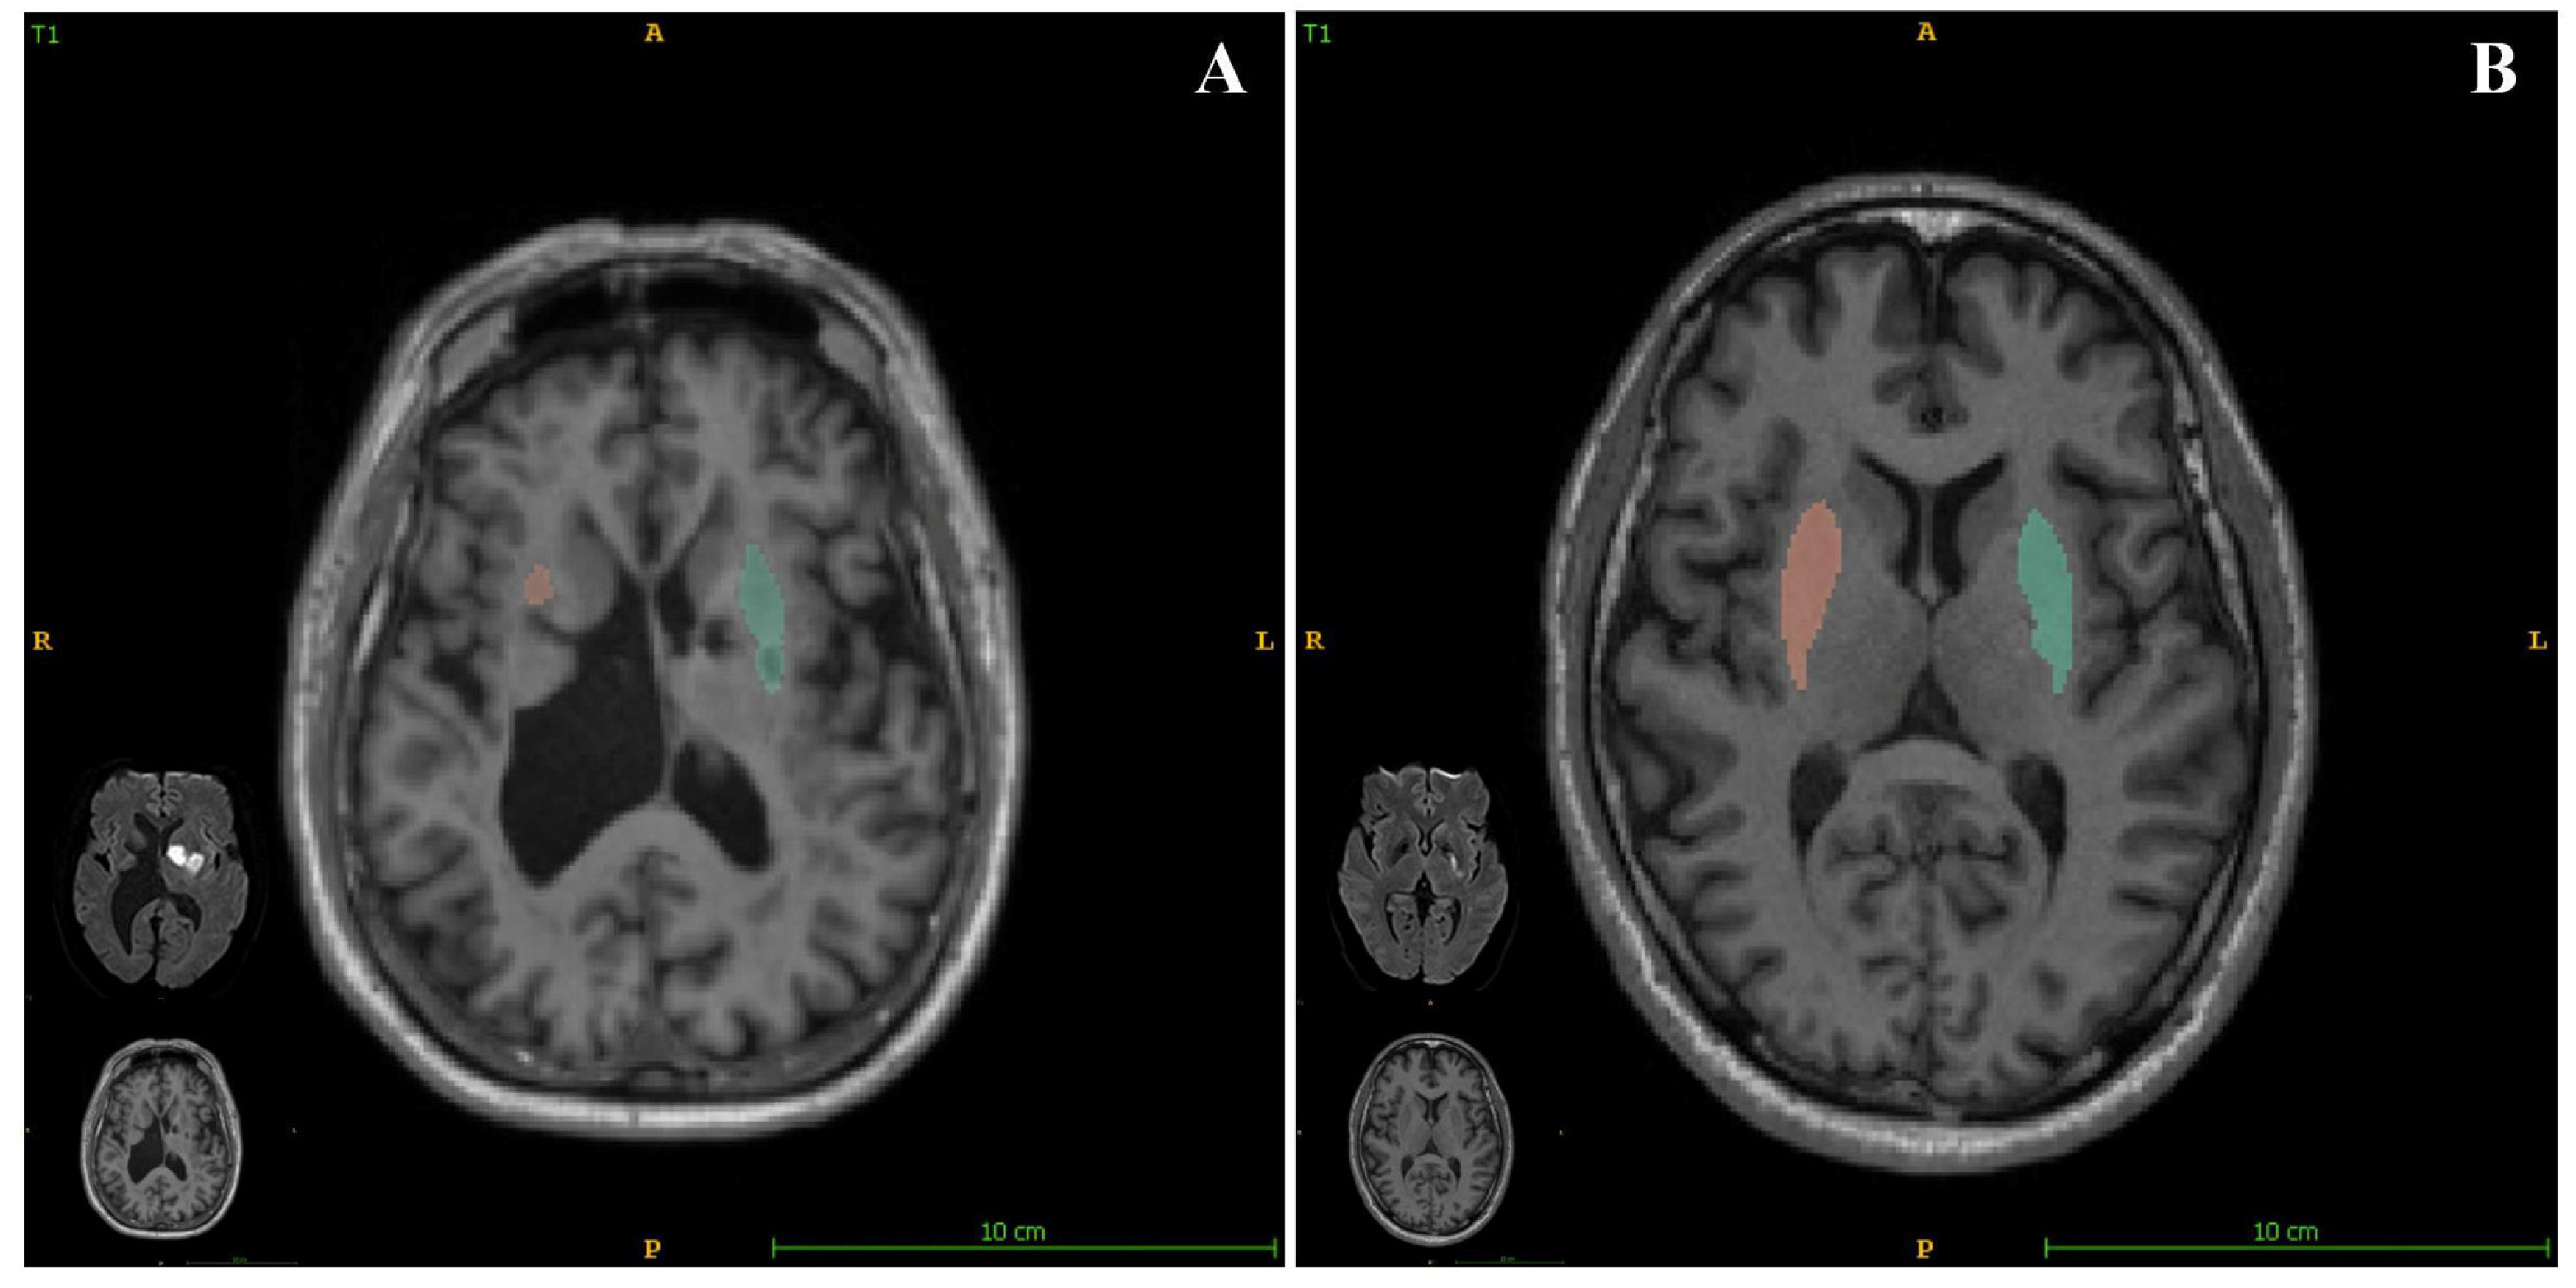

In the present study, we also assessed the relationship between brain structure volumetry and empathy in patients who had experienced acute ischemic stroke. We found that the putamen volume significantly positively correlated with the EQ (Figure 3), with a standardized β value of 0.328. We also obtained data regarding putaminal volumes using quantitative images and present the corresponding relationships of EQ for each participant in the Supplemental materials. These findings show that a smaller putamen volume is associated with a more severe impairment of empathy. As a sequela of stroke may be related to the index stroke and/or SBIs, we assessed the relationship between EQ and the location of SBI (brainstem, cerebellum, basal ganglia, thalamus, or lobes), and found that the location of SBI was not significantly associated with EQ. This implies that a smaller putamen may be more affected both by a combination of stroke and a constitutional condition than by a single factor.

Figure 3.

AccuBrain® (BrainNow Research Institute, Shenzhen, China) was used to quantify of the volume of the putamen and corresponding diffusion-weighted imaging (DWI) in patients with differing empathy statuses. (A) Image of a patient with an EQ of 23 (poorer empathy), with a total putamen volume of 5.53 mL. (B) Image of a patient with EQ of 57 (better empathy) with a total putamen volume of 11.6 mL.